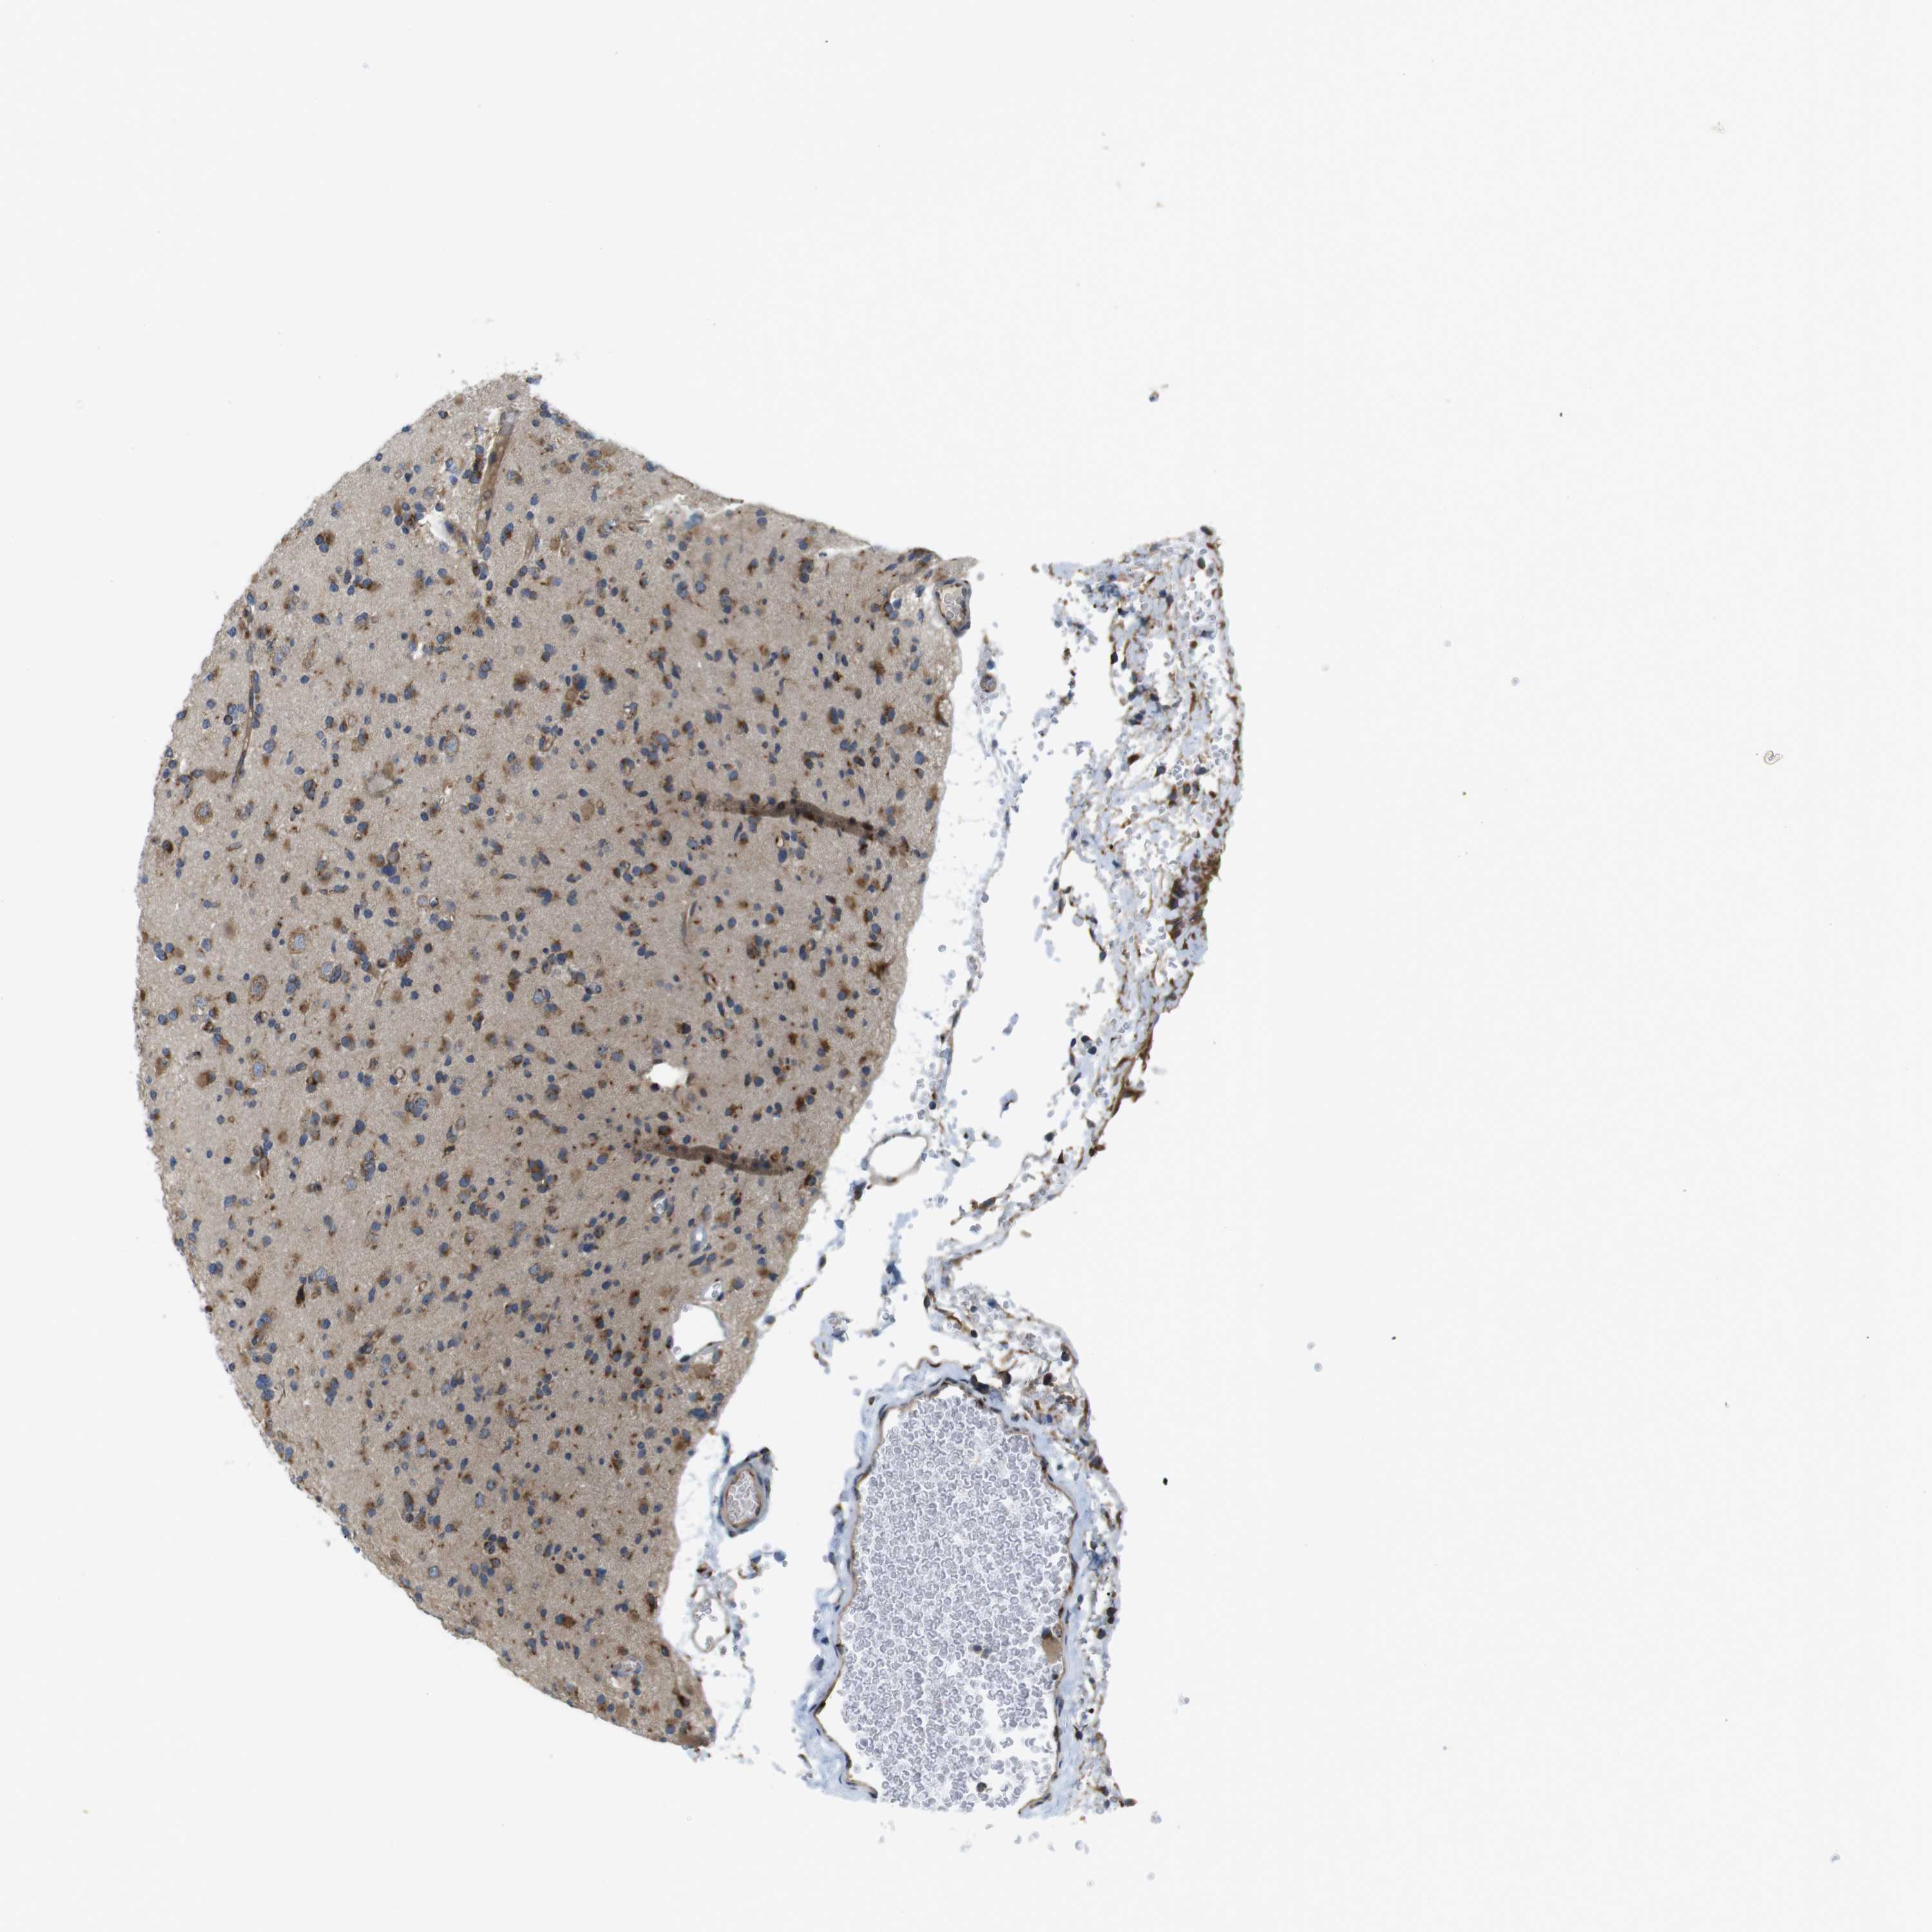

GLIOMA - Protein expressioni

A mouse-over function shows sample information and annotation data. Click on an image to view it in a full screen mode. Samples can be filtered based on level of antibody staining by selecting one or several of the following categories: high, medium, low and not detected. The assay and annotation is described here.

Note that samples used for immunohistochemistry by the Human Protein Atlas do not correspond to samples in the TCGA dataset.

Antibody stainingi

Antibody staining in the annotated cell types in the current human tissue is reported as not detected, low, medium, or high, based on conventional immunohistochemistry profiling in selected tissues. This score is based on the combination of the staining intensity and fraction of stained cells.

Each image is clickable and will lead to virtual microscopy that enables deeper exploration of all samples and also displays staining intensity scores, fraction scores and subcellular localization as well as patient and tissue information for each sample.

Antibody HPA014476

Antibody HPA058645

Staining

High

Medium

Low

Not detected

Intensity

Strong

Moderate

Weak

Negative

Quantity

>75%

75%-25%

<25%

None

Location

Nuclear

Cytoplasmic/membranous

Cytoplasmic/membranous,nuclear

Glioma, malignant, High grade

Glioma, malignant, Low grade